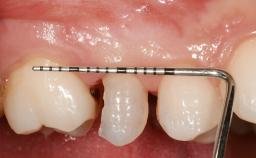

Early Placement of an Implant in a Maxillary Right Central Incisor Site

This 41-year-old female patient was referred to the clinic for the replacement of the right central incisor, since the tooth had developed a root fracture in the long axis that made extraction necessary. The healthy, non-smoking patient was first seen with the tooth still in place. A detailed Esthetic Risk Assessment was performed.The patient was worried about her dental esthetics and had high expectations for a successful treatment outcome from an esthetic point of view. The patient had a medium lip line that displayed parts of the gingiva in the anterior maxilla upon smile.

Mesio-Distal Space Symmetry +/- 1 mm of contra-lateral tooth

Provisional Implant-Supported Prosthesis Prosthodontic margin < 3 mm apical to mucosal margin Prosthodontic margin < 3 mm apical to mucosal margin

Soft Tissue Contour and Volume Slightly compromised